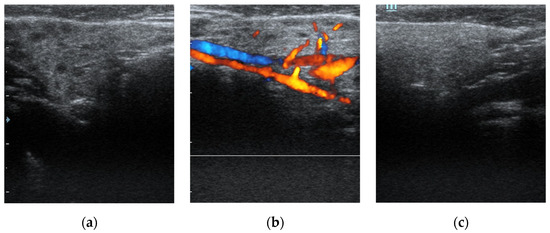

This study included 21 children, of whom eighteen boys and three girls, who were referred to sialendoscopy. There was a preponderance of males with a male-to-female ratio of 6. The mean age of the patient at the time of the procedure was 9.6 ± 5.2 years (range, 2–21). All patients had the US done before the procedure. All clinically symptomatic glands had heterogeneous parenchyma with several hypoechoic nodules observed (Figure 1).

Figure 1. Ultrasound diagnostics of juvenile recurrent parotitis. (a) displays a unilaterally affected parotid gland on the right side of a patient. Note heterogeneous parenchyma with several hypoechoic nodules indicating duct dilatation. (b) demonstrates increased blood flow of the same parotid gland with Doppler mode. In (c), a normal parotid gland on the left side of the same infant is shown as a comparison.